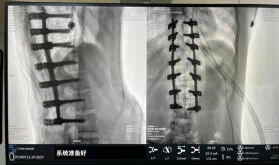

圖為置釘后

據(jù)悉脊柱側(cè)彎手術(shù)治療后可以保持軀干平衡,改善外觀并防止畸形進(jìn)一步發(fā)展。患者的生活質(zhì)量得到提高,進(jìn)而減少脊柱過度畸形可能帶來的疾病的發(fā)生率,外觀上的積極變化往往也能帶來患者心理與精神的積極變化。臨床上會綜合考慮患者的年齡、側(cè)彎程度、進(jìn)展趨勢、骨質(zhì)條件、鄰近節(jié)段情況、手術(shù)節(jié)段等因素,合理采用個性化的手術(shù)方式進(jìn)行治療。然而,由于脊柱神經(jīng)血管密布,手術(shù)操作相對復(fù)雜,手術(shù)難度高、風(fēng)險大,傳統(tǒng)脊柱側(cè)彎的手術(shù)方式往往有較高的神經(jīng)或脊髓損傷風(fēng)險。故此次科室決定開展機(jī)器人輔助導(dǎo)航下脊柱側(cè)彎矯形、植骨融合內(nèi)固定手術(shù)。術(shù)前,醫(yī)生團(tuán)隊在機(jī)器人多維度圖像融合智能手術(shù)規(guī)劃功能的輔助下,預(yù)先規(guī)劃了理想的置釘路徑。術(shù)中,天璣骨科手術(shù)機(jī)器人準(zhǔn)確遵循術(shù)前規(guī)劃,根據(jù)配準(zhǔn)結(jié)果,實(shí)時定位并準(zhǔn)確執(zhí)行置釘操作,所有導(dǎo)針均用電鉆置入,一次性成功,協(xié)助醫(yī)生順利完成手術(shù)。最終,在麻醉科、手術(shù)室密切配合下,歷時3小時成功完成側(cè)彎矯形術(shù),出血量僅500ml。術(shù)后,患者恢復(fù)良好,大小便及下肢神經(jīng)運(yùn)動感覺正常。

此次在充分保證患者安全和手術(shù)效果的前提下使用機(jī)器人輔助下手術(shù)的成功實(shí)施,大大降低了高難度手術(shù)的風(fēng)險,并進(jìn)一步減輕了患者手術(shù)創(chuàng)傷、縮短了康復(fù)時間。這也標(biāo)志著南方醫(yī)院贛州醫(yī)院脊柱外科治療個性化、精準(zhǔn)化、智能化水平進(jìn)一步提升。